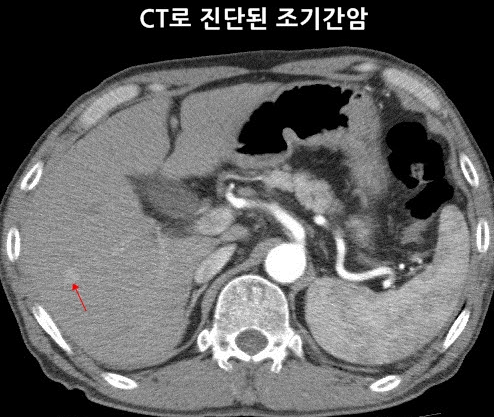

간암을 진단하기 위해서는 알파태아단백 수치를 측정하는 혈액검사와, 초음파, CT, MRI 등 여러 영상 검사를 활용합니다. 때로는 조직검사를 통해 정확한 진단을 내리기도 합니다.